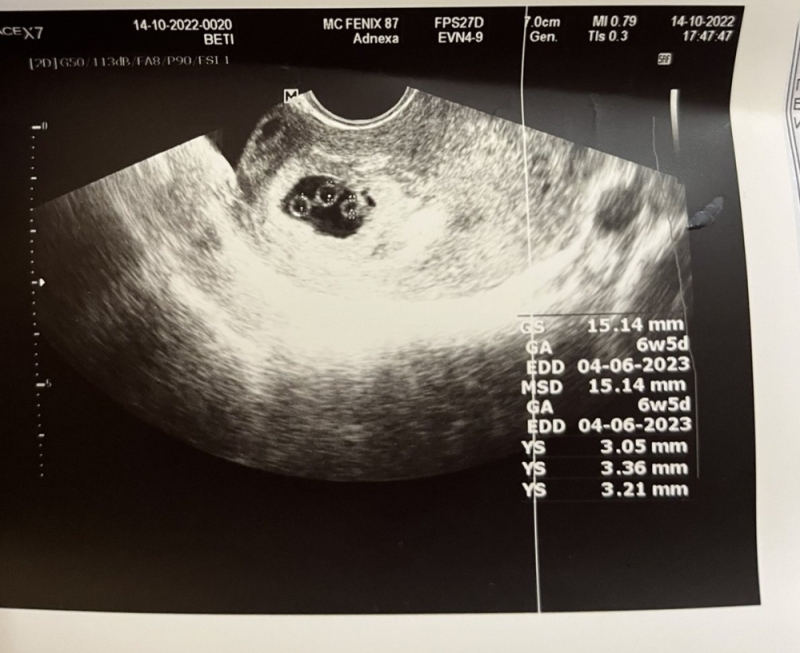

Радослав и Бетина официално стават семейство през 2017 г., а преди три години и половина се ражда и техният първи наследник – Никола. Както и много двойки, двамата след време започват да мислят и за второ дете. Каква обаче е изненадата им, когато миналата година разбират, че Бетина е бременна… с тризнаци.

Щастието и страхът изведнъж започват да се преплитат силно, тъй като се оказва, че те са еднояйчни, а това носи риск, както за бебетата, така и за майката. Няколко лекари дори препоръчват да се направи аборт, но двамата просто не могат да се решат на тази тежка стъпка.

Раждането на еднояйчни тризнаци е истински феномен, като според някои статистики това се случва веднъж на 200 милиона случая или дори повече. В България последният известен такъв е от 2012 г. във Враца, след като преди това не е имало подобен от 25 години.